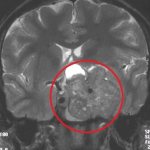

Диагностика рака головного мозга

Раковые опухоли хорошо поддаются лечению, если диагностика была произведена быстро, качественно и на ранних стадиях развития заболевания. Современная медицина использует большой набор методов диагностики рака мозга, среди них наиболее популярны следующие:

• рентгенологические исследования, компьютерная томография (КТ) с применением контраста, магниторезонансная томография (МРТ), позитронно-эмиссионная томография (ПЭТ), электроэнцефалография;

Статистика утверждает, что ежегодно только в России выявляют более 30000 случаев возникновения раковых заболеваний головного мозга. Важно понимать, что первые признаки этого недуга совсем безобидны. Многие предпочитают бороться с головной болью, усталостью и депрессией собственными силами, либо вообще не берут во внимание усиливающиеся симптомы. Однако пренебрегать здоровьем не стоит. Чтобы не пропустить начало заболевания, рекомендуется сделать МРТ и пройти должное обследование.